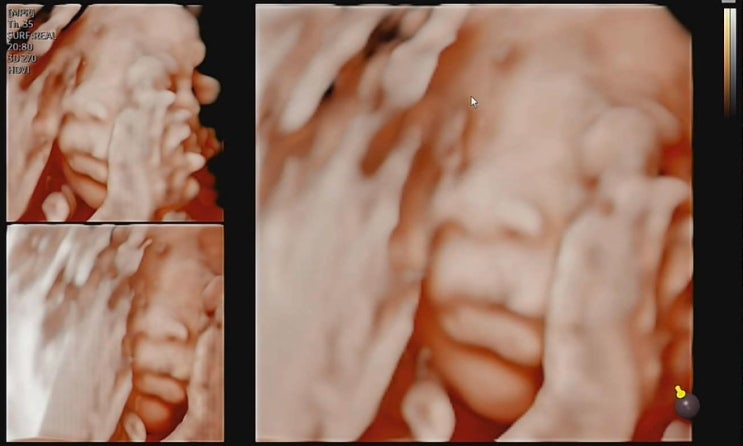

26주임산부 일상일기/임당검사/입체초음파/26주차 증상

26주차 증상 시도때도없는 다리저림/붓기 낮과 밤이 다른 배 크기 배 간지러움 간헐적인 배 근육이 찢어지...